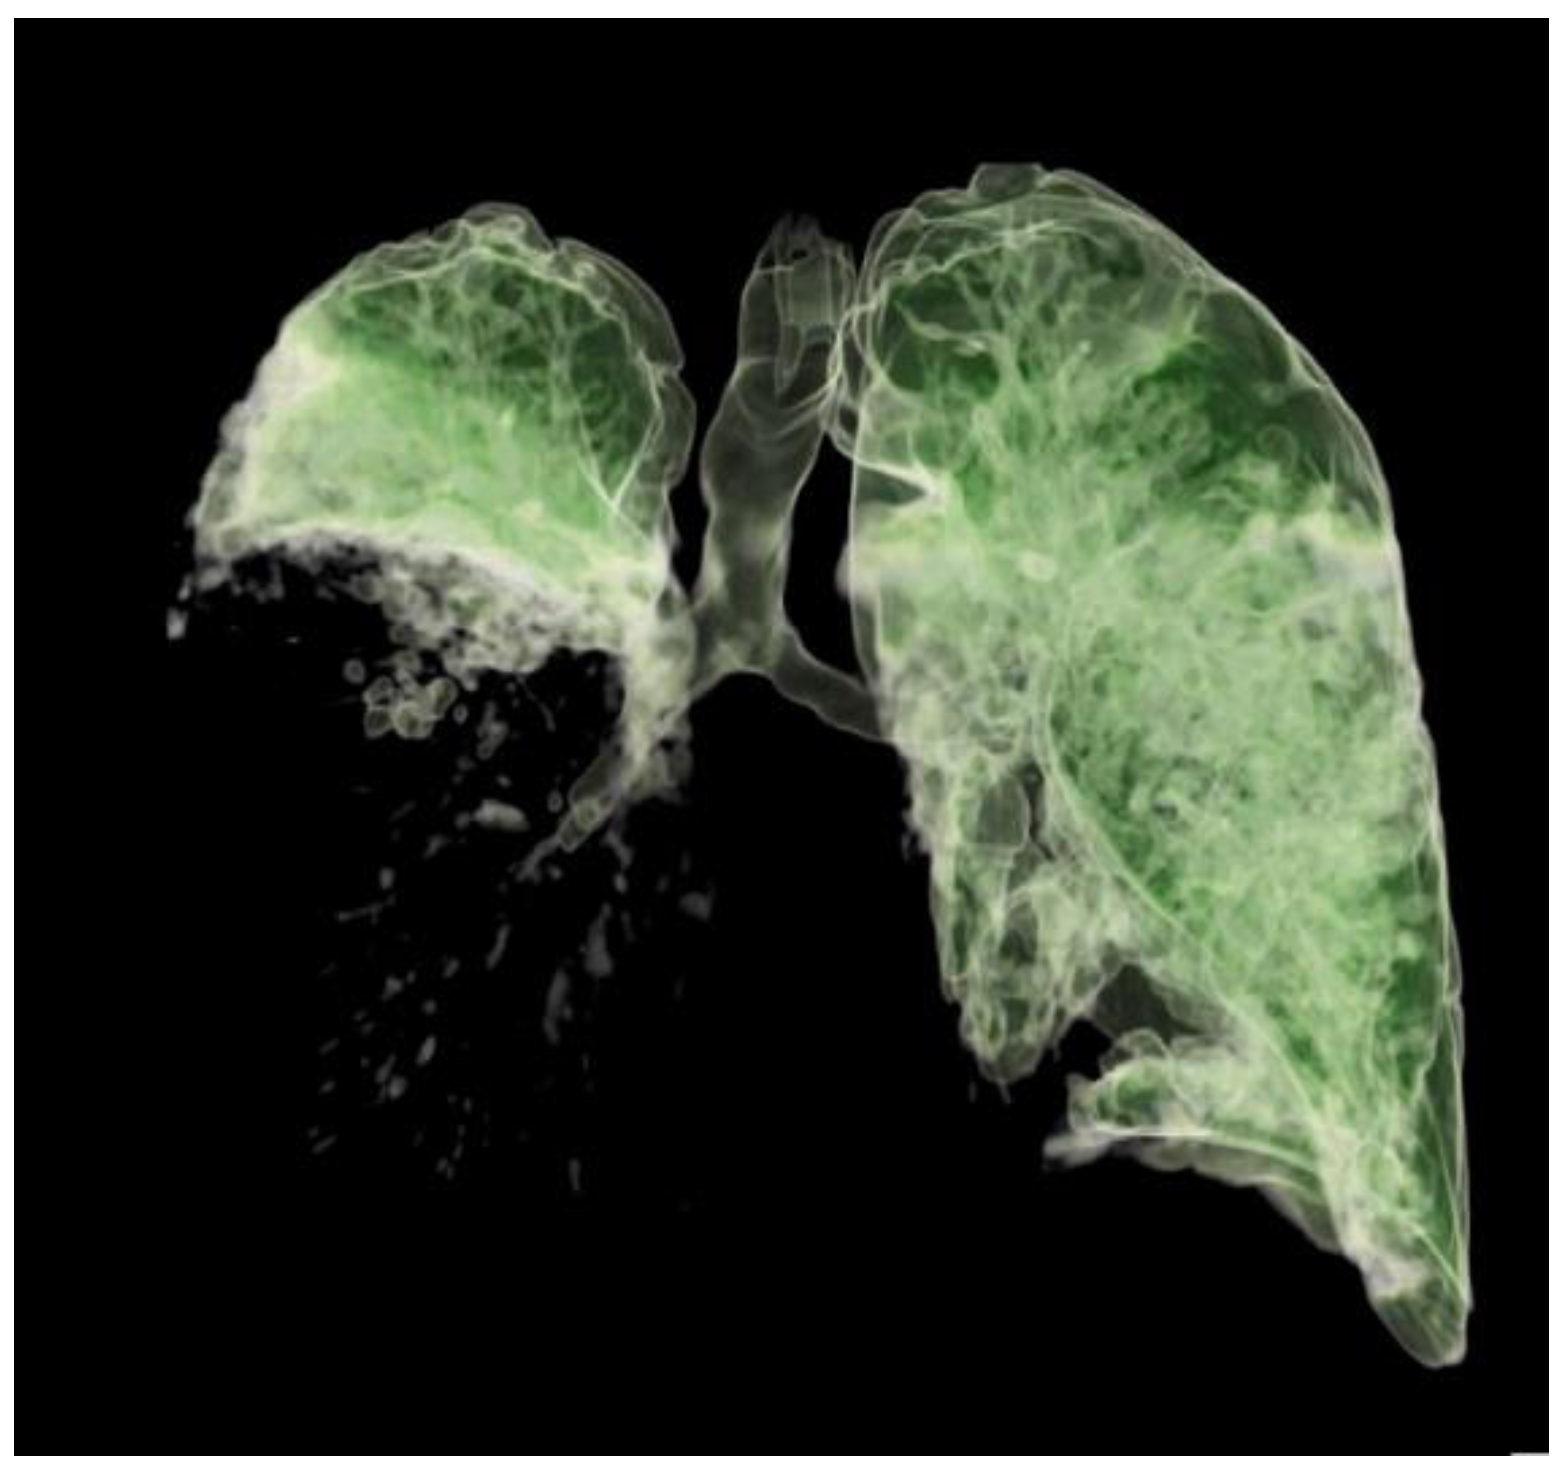

The patient's clinical condition improved in the following days, and he continued to breathe spontaneously with oxygenation. The control chest radiograph of the lung revealed complete expansion of the lung parenchyma with lung infiltrates on the medial and lower lung lobes. The patient's general condition gradually improved, and he was transferred to the ward on day 19 after ICU admission with supplemental oxygenation of 4 L O2/min via the nasal catheter and frequency of 18–20 breaths/minute with adequate oxygen saturation of 95–97%. The thoracic drain was removed on the ward (Figure 3).

Figure 3. A 3D computed tomography scan of the lungs 25 days after admission to the Intensive Care Unit.